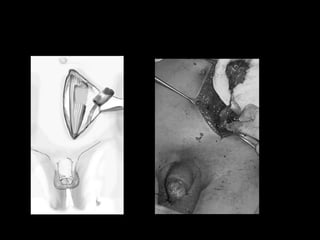

Cerrado

• Fractura de pene

Fractura

Amputación

Tratamiento

• Contusion con hematoma

Avulsion

Amputacion